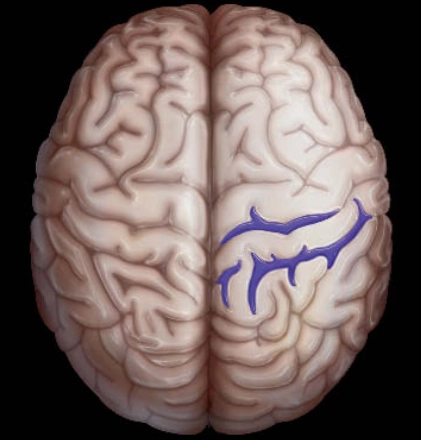

• Nhiễm sắt bề mặt vỏ não (Cortical Superficial Siderosis- cSS)